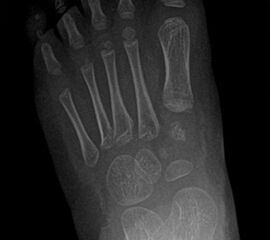

Röntgen Fuß AP und seitlich im Stand oder belastungssimuliert (Abb.1,2).

• Röntgen des dargestellten Falles 3 Monate post OP (Bild 25,26)